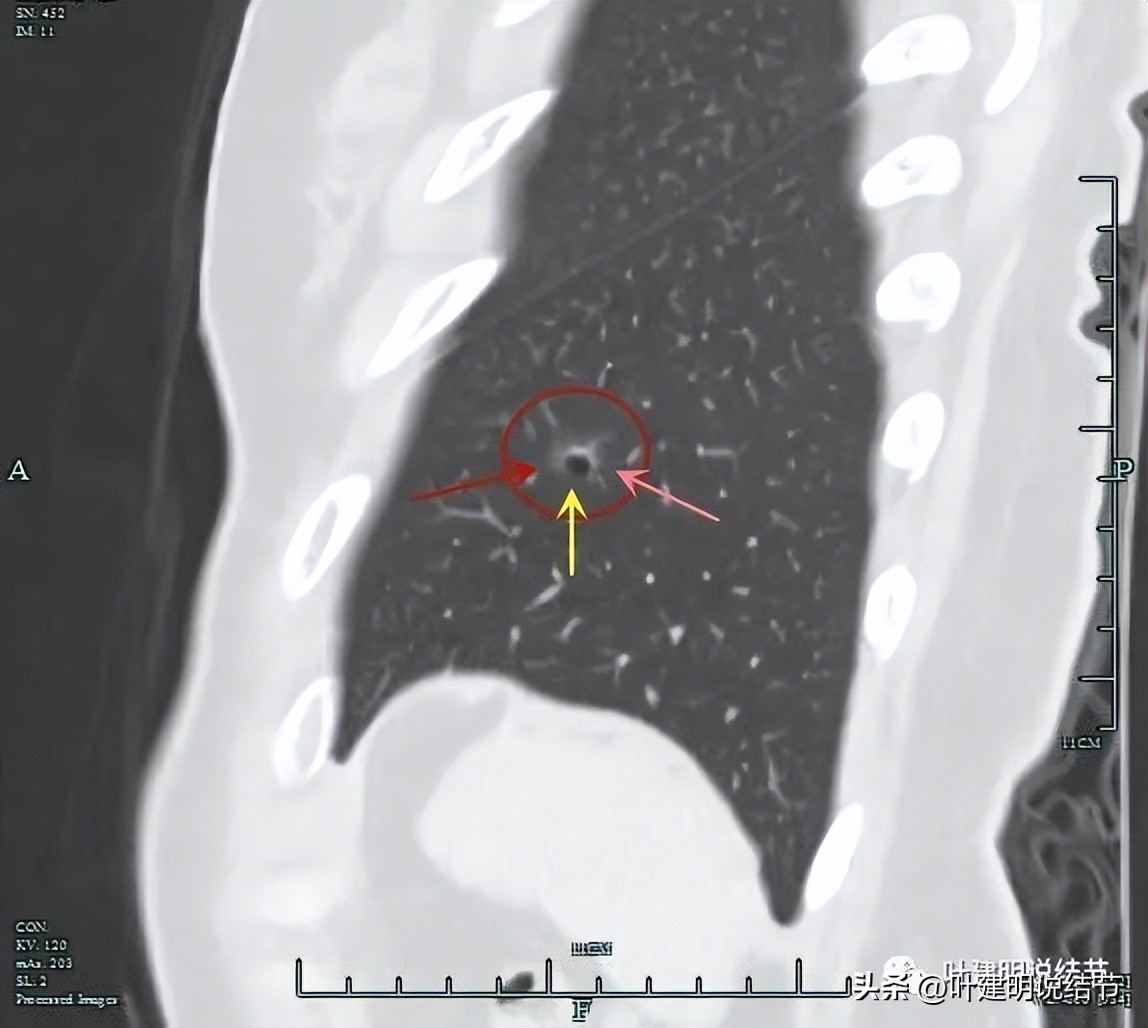

上图显示了病灶轮廓与瘤肺边界其实还是清楚的。

部分边缘有毛刺征可见。

显示明显的血管征与血管异常增粗和壁毛糙。

上图显示病灶轮廓较清,有锐利细毛刺征,灶内有弯曲血管穿行。

囊壁有少许是偏实性成分的,如粉色箭头所示。

血管增粗进入并散开来。

血管在病灶内发出分支。